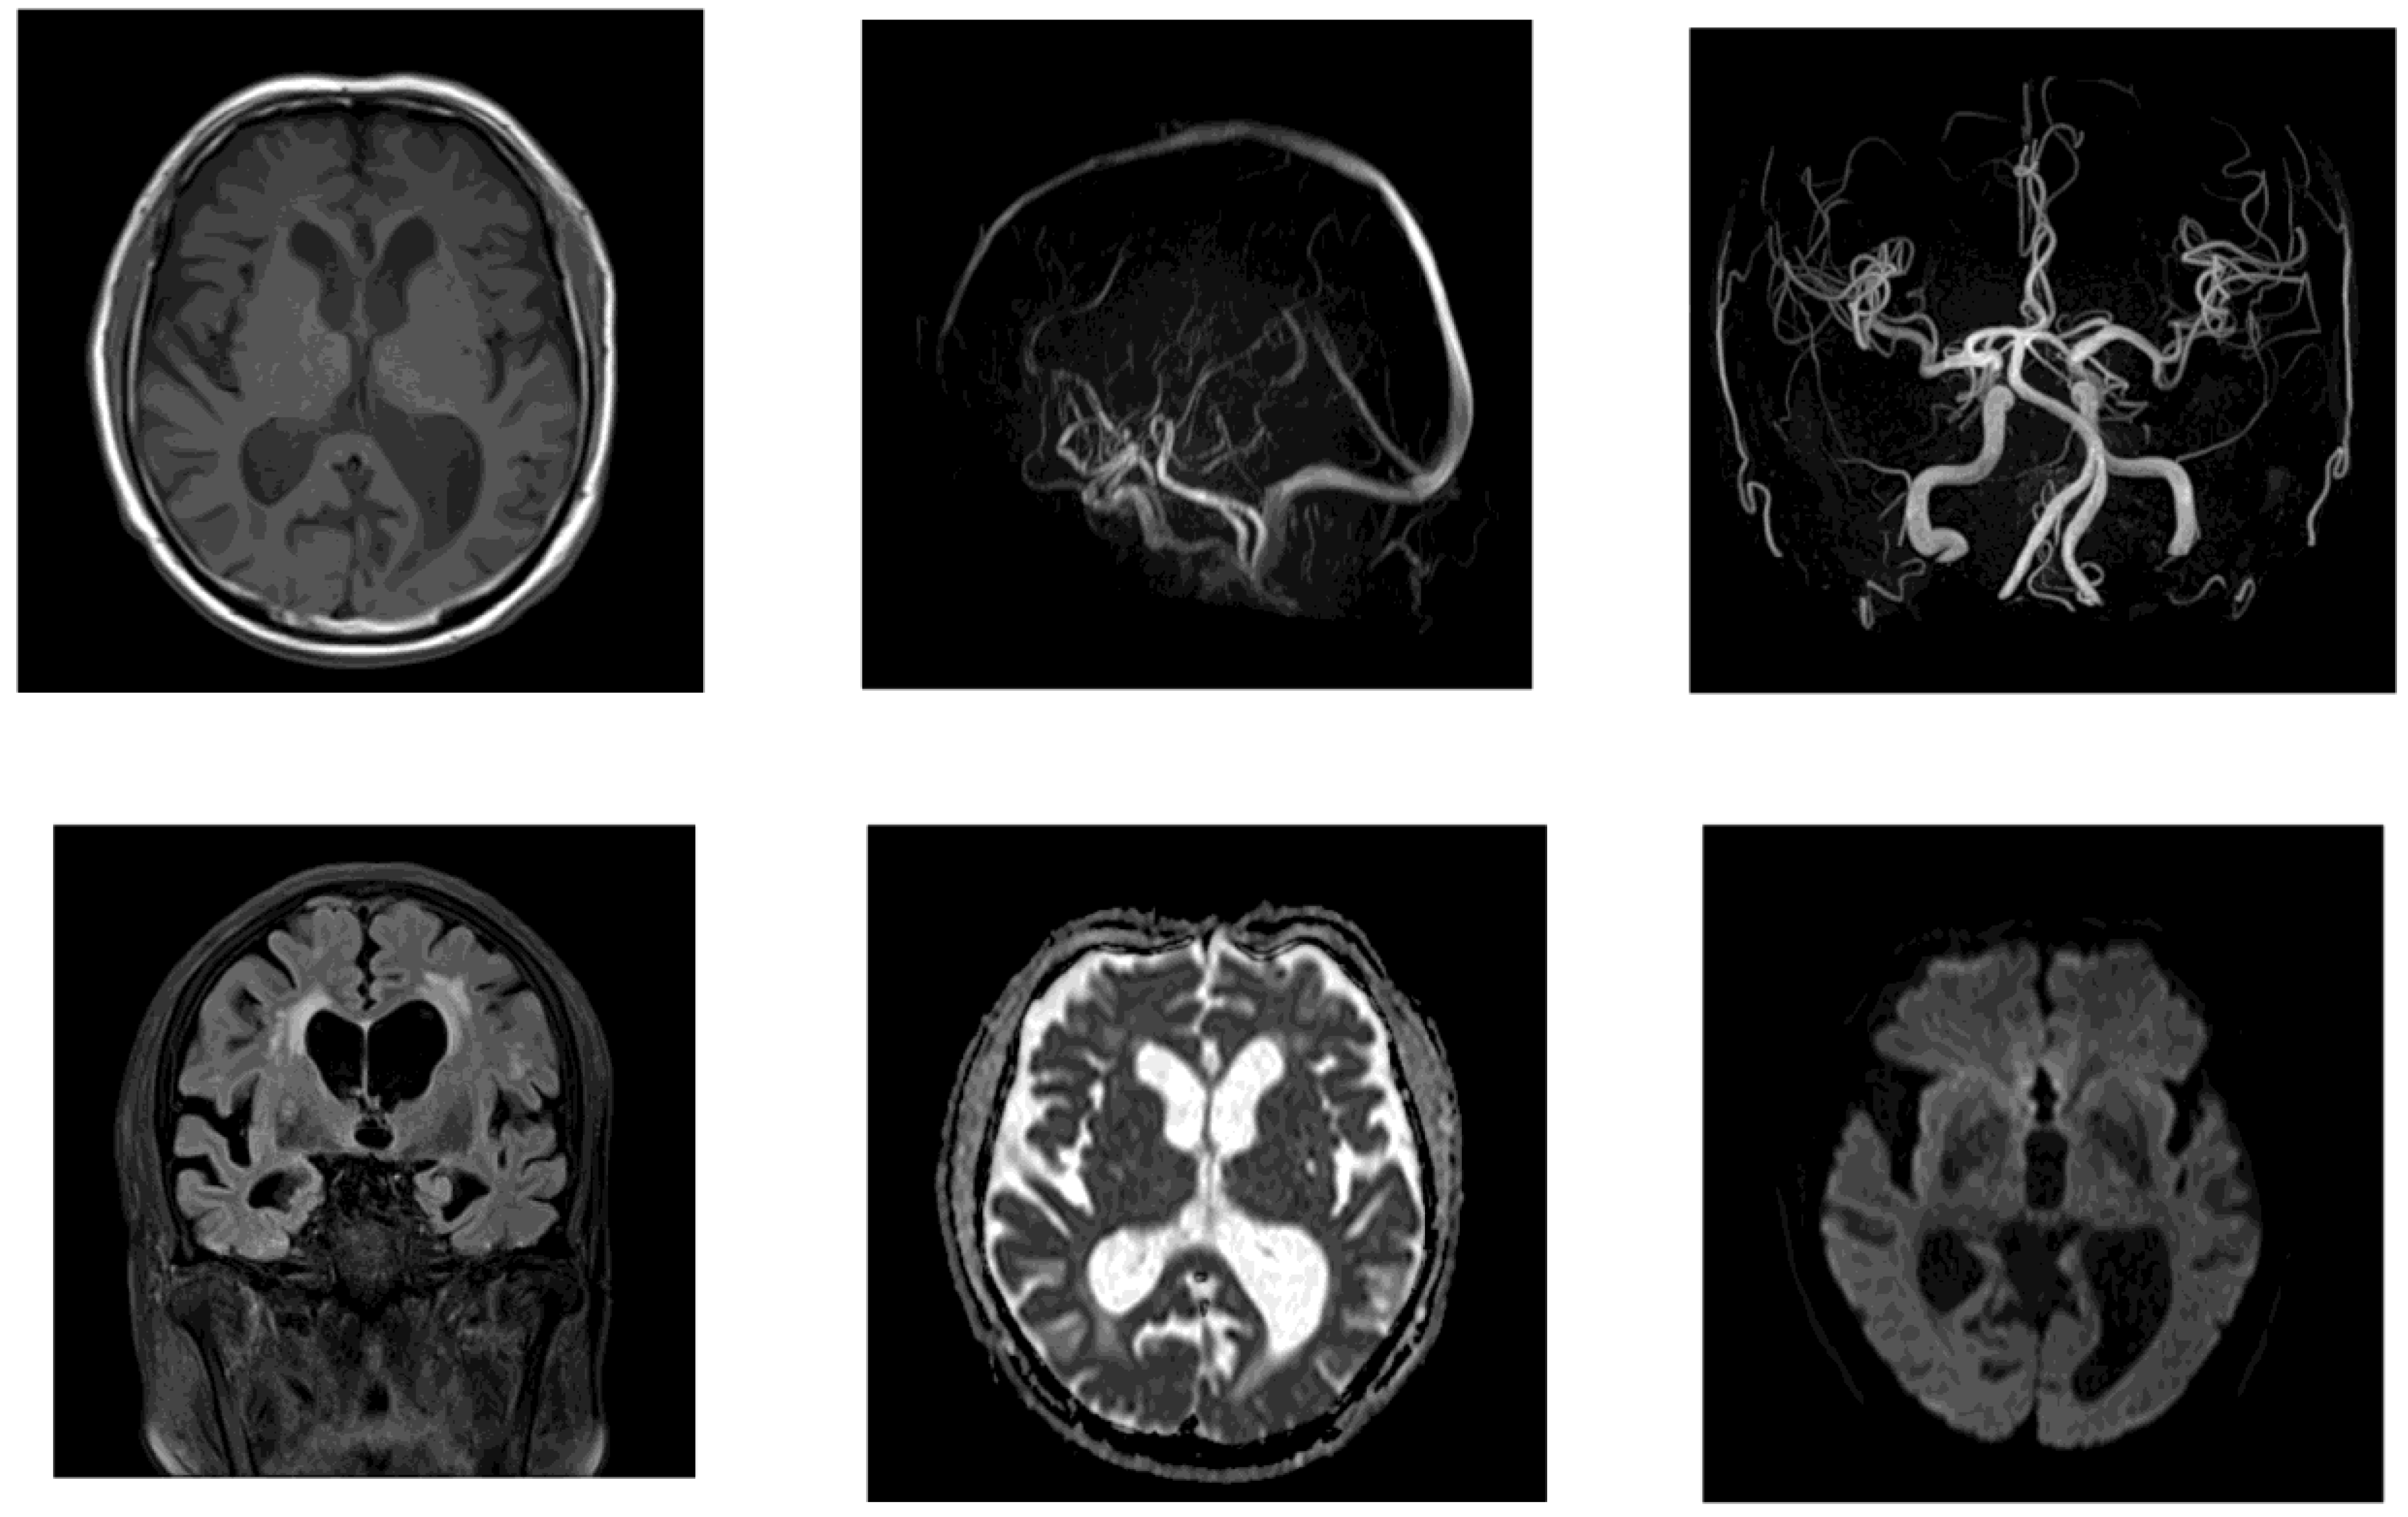

Initial management included the continuation of antibiotic therapy along with intravenous ozagrel sodium for antiplatelet effects, followed by the initiation of oral clopidogrel. A tap test was performed on day 21 of the patient’s hospitalization. His gait velocity improved from 1.255 to 1.339 steps/s thereafter, and his MMSE score increased from 11 to 16, suggesting responsiveness to CSF drainage. Lumber MRI showed spinal canal stenosis. On day 41, a right-sided VP shunt was inserted. Postoperatively, the patient demonstrated a significant improvement in independent ambulation (Table 4). Mild improvements in cognitive function and urinary symptoms were also observed. A follow-up CT performed on day 50 revealed a reduction in ventricular size (Figure 5).

Figure 5. Follow-up head CT after shunt surgery in Case 2. CT on postoperative day 9 showed a reduction in ventricular size vs baseline, indicating a favorable radiological response to VP shunting.